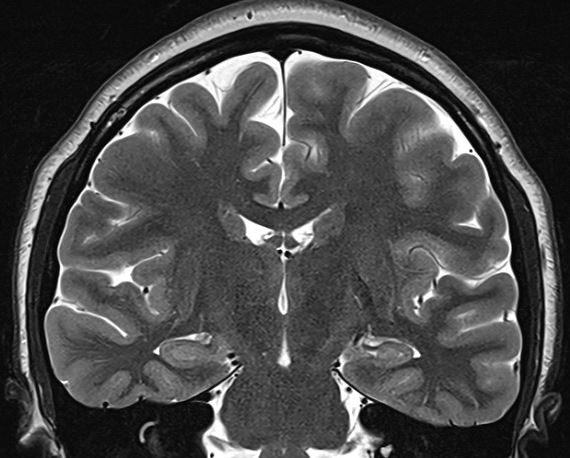

Here are some phantom spike-and-wave discharges from last week. The patient is a young adult.

The above waves appear exclusively while awake and during very light sleep, but none are seen during deeper sleep, including stage II. For what it's worth, there is no history to suggest generalised epilepsy; The history provided by patient and the family suggests right temporal lobe epilepsy of 16 years duration; The patient is entirely unaware of seizures. The father's cousin (mid 50's) has epilepsy, manifest with GTCS without warning, since childhood. The inter-ictal EEG recording is normal. The patient has had 4 recorded seizures lasting 1-3.5 minutes, all of which appear over the right mid-temporal region (T4) on scalp EEG recordings; neither the patient, other patients nor the nursing staff noticed anything when she had these seizures, which were discovered on systematic scrutiny of the EEG recording. The patient and the family think that the seizures are well controlled, but that memory is poor. This likely is a consequence of intermittent amnestic seizures, as these appear on the scalp EEG recordings without a change in the antiseizure medication. The MRI scan of the brain is normal.